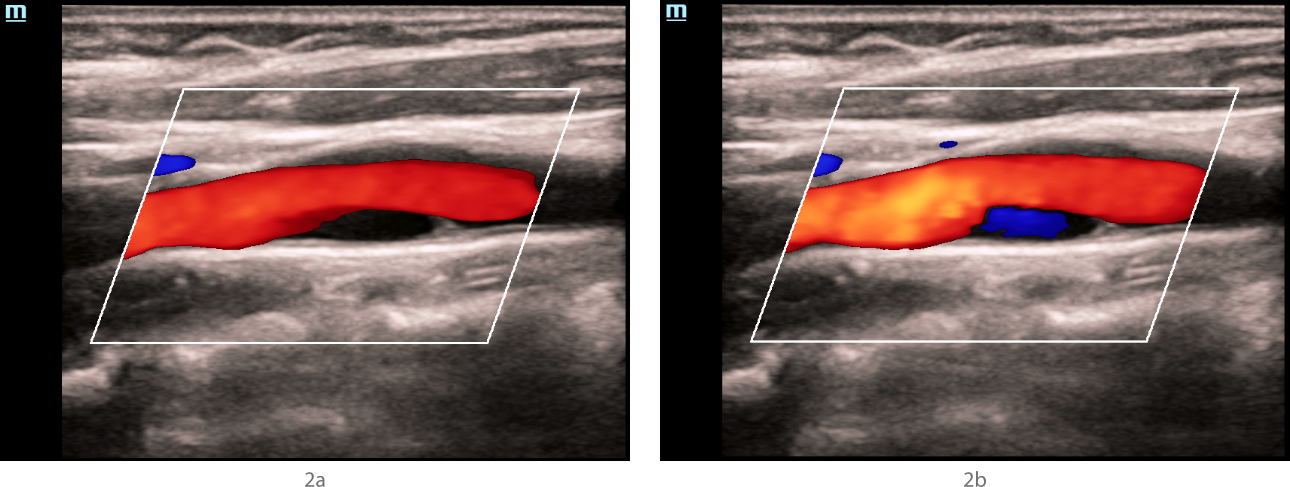

In the mode of color Doppler mapping, in the bifurcation of the left common carotid artery along the posterior wall, an anechoic zone with a smooth surface, about 1 cm long, was visualized (Fig. 2a), which was partially filled with blue blood flow (as opposed to red in the rest of the carotid arteries) (Fig. 2b). The "aliasing" effect over the zone of detected changes was not detected. In the spectral Doppler mode, in the bifurcation of the common carotid artery, the velocity parameters of blood flow were within normal limits, no areas with local changes in hemodynamics were detected (Fig. 3).

aotid-web-v-flow-fig2-pc

Fig 2. Ultrasound of the carotid sinus in the mode of color Doppler mapping.

In the bifurcation of the common carotid artery along the posterior wall, an anechoic structure is visualized, having a hyperechoic contour in the proximal shoulder, and partially filled with blue blood flow during different phases of the cardiac cycle and when the device settings are changed.

The results of ultrasound in the FSBI NCN. According to seroscale and Doppler ultrasound modes, hyperechoic linear structures were detected in the bifurcation of the common carotid arteries on both sides, with a large narrowing of the vessel lumen on the left, which could be a sign of intimal detachment and suggest dissection or a local form of fibromuscular dysplasia. An anechoic staining defect of the vessel lumen was detected behind the hyperechoic structure in the distal direction on the left in the CDK mode, which was partially filled with the color (blue) opposite to the main flow direction when changing the settings of the device and the phase of the cardiac cycle. Since it was not possible to completely paint the anechoic defect with a color stream, while not flooding the lumen of the common carotid artery with adjacent structures with color, it was impossible to exclude the presence of an atherosclerotic plaque in a typical place of its formation with a tire visualized in its proximal part or, but less likely, a parietal thrombus. The absence of an increase in the rate of blood flow and local changes in hemodynamics indicated the hemodynamic insignificance of structural changes in the carotid arteries on both sides.